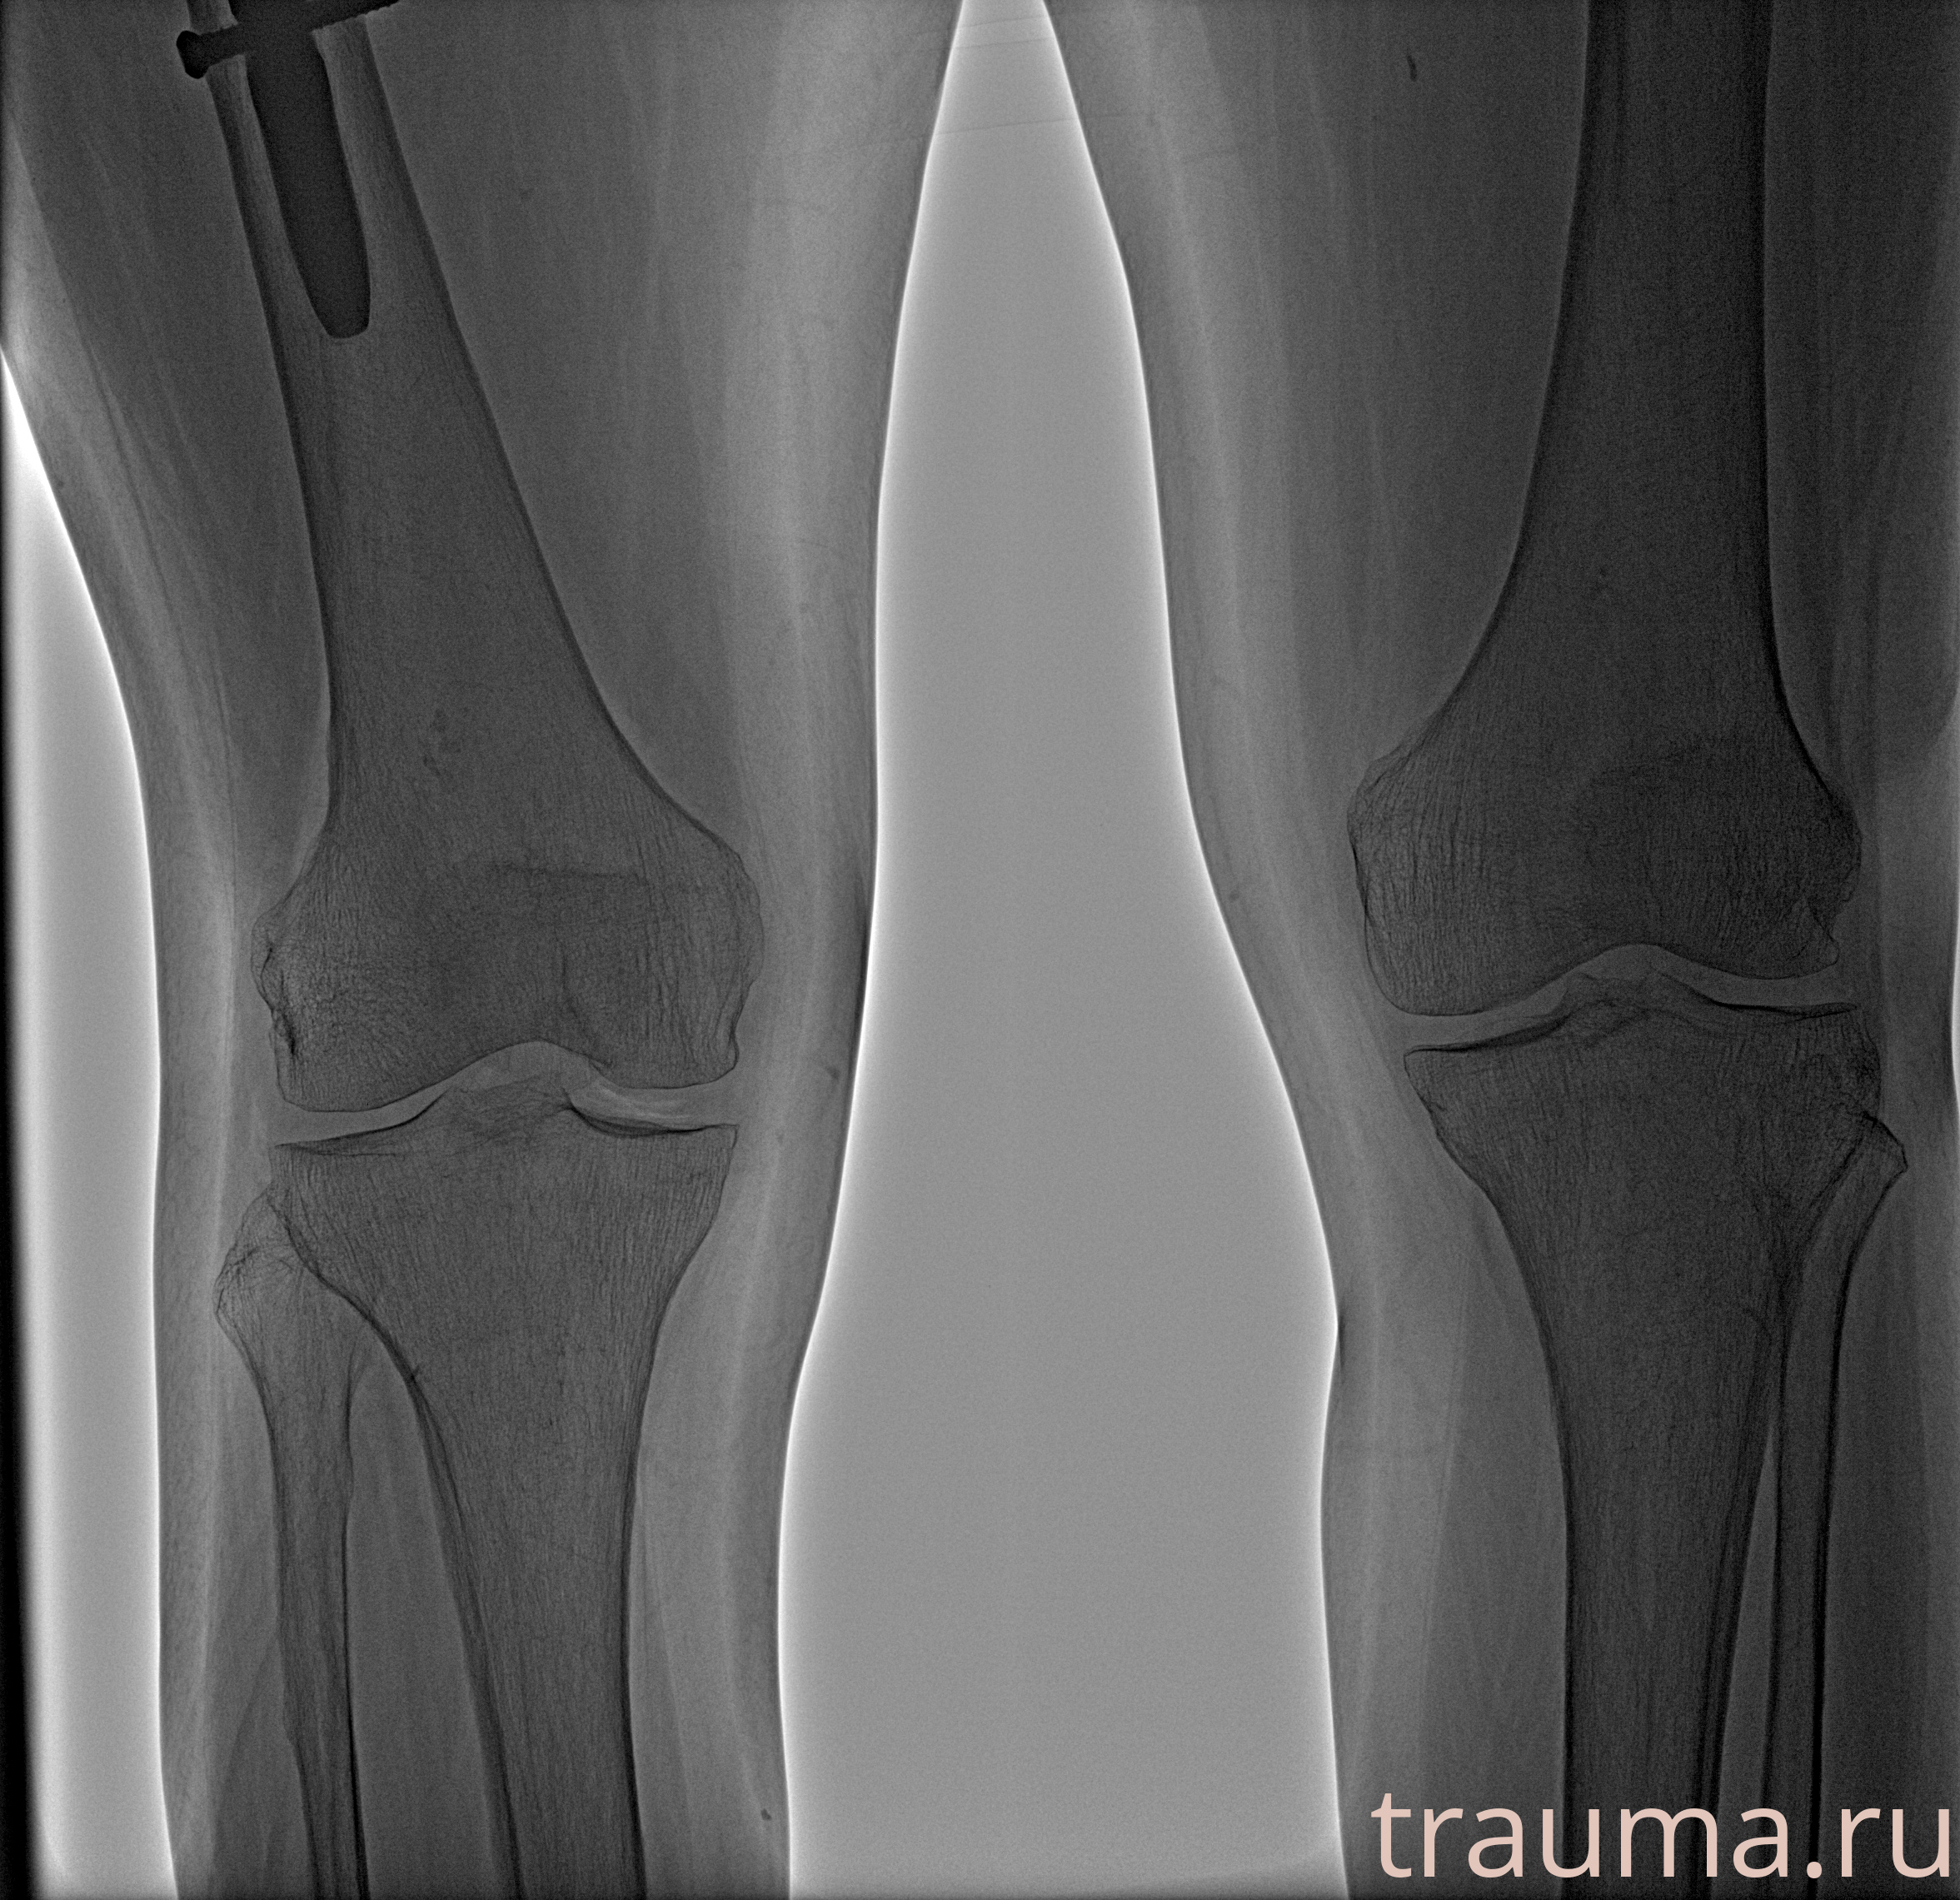

/  Касимова

Рентгенограммы

Рентген на дому: по вашему адресу приезжает врач-рентгенолог, травматолог-ортопед с мобильным рентгеновским аппаратом, проводит диагностику травмы или заболевания, делает необходимые рентгенограммы, дает рекомендации по дальнейшему лечению. Получить качественные снимки в домашних условиях возможно благодаря уникальной методике, разработанной МосРентген Центром для института  Склифосовского